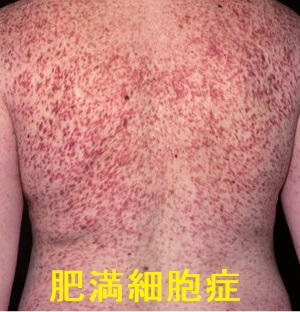

肥満細胞症は肥満細胞が皮膚などの臓器に異常増殖する病気です。小児65%・成35 %で、成人は20~40歳で発症します(J Invest Dermatol1991;96:32S-38S;discussion 38S-39S.)

体幹四肢の皮膚に多発する褐色斑(色素性蕁麻疹)を擦過すると数分後に膨疹を生じるDarier徴候(ダリエ徴候)が特徴的。

種々の刺激により肥満細胞の脱顆粒が起こるとアレルギー反応→アナフィラキシーショックもあり得ます。

肥満細胞白血病に移行する事もあります(Blood 2017;129:1420-1427.)。

発作的な顔面紅潮は、神経内分泌腫瘍(カルチノイド症候群・褐色細胞腫・甲状腺髄様癌)との鑑別が必要(J Am Acad Dermatol. 2006 Aug;55(2):193-208.)。